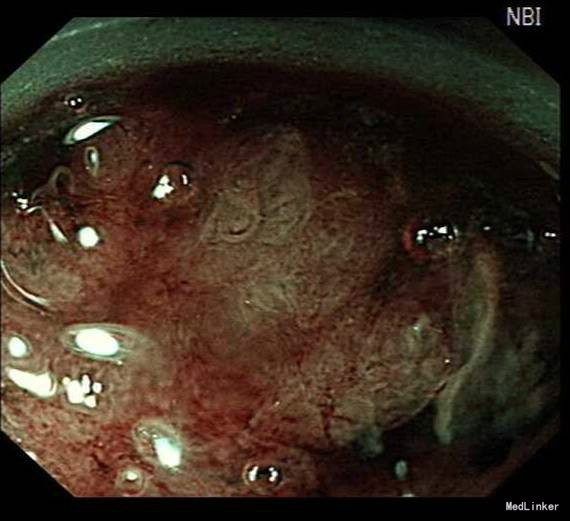

诊疗经过:入院后经过术前检查,行放大内镜检查和超声内镜检查,超声内镜提示:胃窦病灶未突破粘膜下层,诊断考虑:胃早癌。于10月30日行内镜下胃ESD术,术顺,安返病房。经过过制酸、补液等对症处理,3天后患者顺利出院。

随访:出院后2周,电话随访患者,一般情况良好,无不适主诉。 讨论:该患者胃镜见一胃窦前壁粘膜隆起,表面粘膜粗糙,病理示:慢性萎缩性胃炎,伴部分腺体中重度不典型增生,局灶重度不典型增生,超声胃镜病灶未突破粘膜下层,有胃ESD手术指征,故行全麻下胃ESD术。术后病理:胃窦前壁肿瘤:腺上皮高级别上皮同瘤,部分癌变,病变大小1.5*1.1*0.3cm,基底及切缘未见癌。说明手术成功,切缘及基底均无肿瘤侵及。对于早癌患者我们完全可以通过采用ESD方法治愈患者,胃镜下切除早癌较腹腔镜创伤更小。我和患者解释时是这样说的:腹腔镜是微创,而我们内镜下ESD则是微微创。